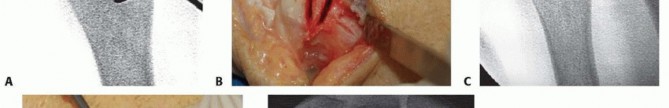

TECH FIG 2 • A. Dorsal compression plate in dorsal position. Proposed osteotomy drawn. The oblique osteotomy angle is about 45 to 60 degrees and it is typically 5 to 6 cm proximal to the ulnar styloid. B. Synthes small distractor apparatus secured along the ulnarmost border with four 2.5-mm threaded Kirschner wires. The kerf (amount of bone resected by the saw blade itself) must be taken into account when planning the site of the second osteotomy cut to determine accurately the total amount of bone removed.Kerf thickness varies based on the specific blade used and can be obtained from the manufacturer.7Make the second parallel osteotomy cut proximal to the first, using a freehand technique, and remove the wafer of bone.Distract the osteotomy site and inspect it to ensure that there are no bony excrescences or residual uncut bone margins, which could interfere with apposition of the fragments.

Dial down the small distractor apparatus to achieve compression at the osteotomy site and bone-to-bone abutment (TECH FIG 4A).A reduction clamp is valuable in guiding and then securing the fragments as compression is applied.Examine the radioulnar relationship under fluoroscopy to ensure adequate correction of ulnar variance and DRUJ congruence.Additional bone resection followed by repeat reduction and compression can be easily achieved if necessary.Again, place the Synthes nonlocking LC-DCP on the dorsum of the ulna, and drill screw holes using a compression or neutral drill guide.With the exception of the interfragmentary lag screw hole, directly over the osteotomy site, all screw holes in the plate are drilled using a 2.5-mm drill followed by a 3.5-mm tap (unless self-tapping screws are used).First, secure the plate with static screws to the fragment with the acute angle (point) on the side away from the plate (palmar in this case, using a dorsal plate).Reduce and secure the osteotomy, and then place compression screws in the other fragment, the one with the acute angle (point) adjacent to the plate.Place the first compression screw in the second hole away from the osteotomy. Fill the remaining more proximal holes with either compression or static screws.As a final step, insert an interfragmentary lag screw through the osteotomy via the hole in the plate directly over the osteotomy (TECH FIG 4B).Pass a 3.5-mm drill only through the near cortex, followed by a 2.5-mm drill through the far cortex. Tap this hole and fill it with a 3.5-mm bone screw.Once proximal and distal stabilization has been achieved, it may be necessary to remove the 2.5-mm pins to fill the remaining screw holes.

TECH FIG 4 • A. Osteotomy compression. B. An interfragmentary lag screw is placed through the plate.